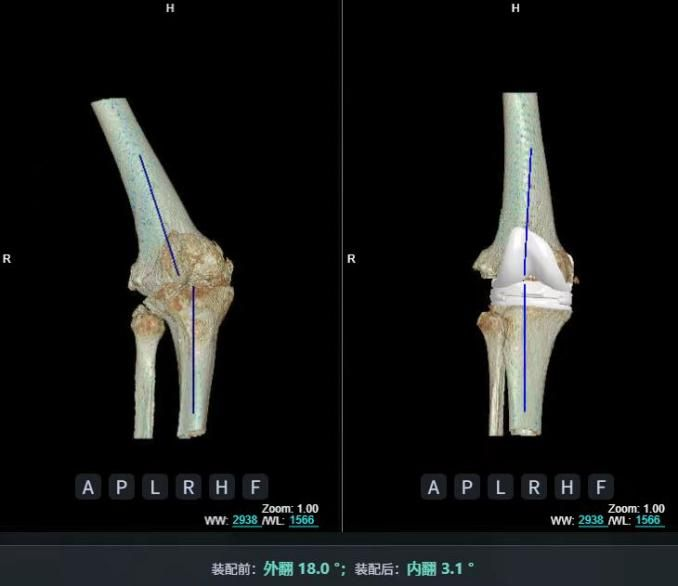

3D打印截骨導板輔助技術(shù)治療骨關(guān)節炎,是結合數字化醫學(xué)與3D打印的精準方案:通過(guò)患者CT或MRI影像數據,設計并打印個(gè)性化截骨導板,輔助醫生術(shù)中精準定位截骨位置和角度,優(yōu)化手術(shù)效果。

例如,2025年3月,福建醫大附屬協(xié)和醫院馮爾宥主任團隊就用該技術(shù)完成一例高難度踝關(guān)節置換術(shù),為踝關(guān)節創(chuàng )傷性骨關(guān)節炎患者治療。[7]

術(shù)中借助3D打印截骨導板精準截骨、安放假體,僅需小切口即可完成畸形矯正與假體植入;結合加速康復理念,患者術(shù)后第3天便能借助助行器下地,康復科定制的漸進(jìn)式訓練計劃助力其預計1個(gè)月內獨立行走,術(shù)后X線(xiàn)顯示假體位置理想、關(guān)節力線(xiàn)完美恢復。

比較傳統踝關(guān)節置換術(shù)依賴(lài)術(shù)中反復透視調整截骨角度,存在操作復雜、輻射暴露多、假體匹配等不足,3D打印假體踝關(guān)節置換術(shù)可將手術(shù)誤差控制在毫米級,術(shù)中透視次數減少50%以上,手術(shù)時(shí)間縮短至1-2小時(shí),患者術(shù)后次日即可開(kāi)始康復訓練。